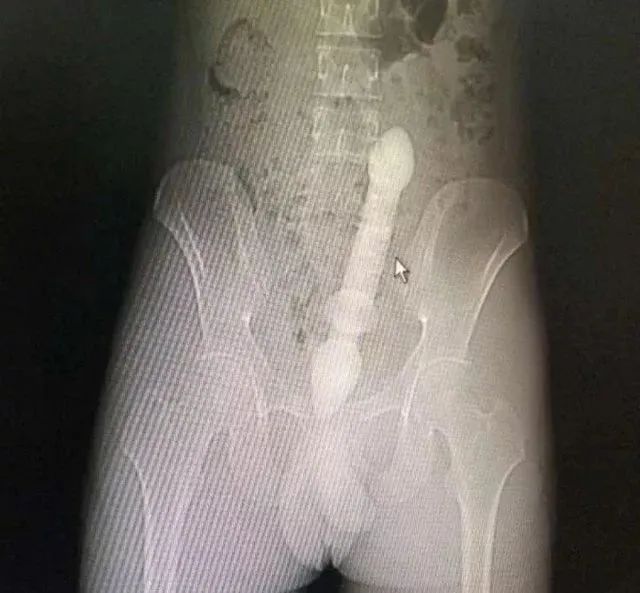

一位50多岁的男子发现了这种新奇玩法,把重达10斤的哑铃塞进了肛门。

医生会通过一系列检查如直肠指诊、X线来确定体内的异物是什么,在什么位置,这一点非常关键,因为只有搞清楚里面的真实情况,医生才能找到合适的方法把异物取出。 一些小的、圆的异物,像小跳蛋、玻璃球,一般可以自行排出。 如果不行的话就需要在腰麻等麻醉下充分扩肛后取出,对于果壳、鱼刺与粪便结成的大团块,可灌入石蜡油后用卵圆钳夹碎,分块取出。